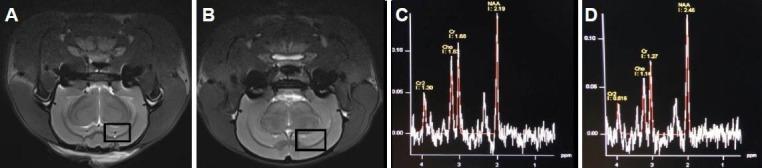

3.0T magnetic resonance spectroscopic imaging is a commonly used method in the research of brain function in Alzheimer's disease. However, the role of 7.0T high-field magnetic resonance spectroscopic imaging in brain function of Alzheimer's disease remains unclear. In this study, 7.0T magnetic resonance spectroscopy showed that in the hippocampus of Alzheimer's disease rats, the N-acetylaspartate wave crest was reduced, and the creatine and choline wave crest was elevated. This finding was further supported by hematoxylin-eosin staining, which showed a loss of hippocampal neurons and more glial cells. Moreover, electron microscopy showed neuronal shrinkage and mitochondrial rupture, and scanning electron microscopy revealed small size hippocampal synaptic vesicles, incomplete synaptic structure, and reduced number. Overall, the results revealed that 7.0T high-field nuclear magnetic resonance spectroscopy detected the lesions and functional changes in hippocampal neurons of Alzheimer's disease rats in vivo, allowing the possibility for assessing the success rate and grading of the amyloid beta (1-40) animal model of Alzheimer's disease.